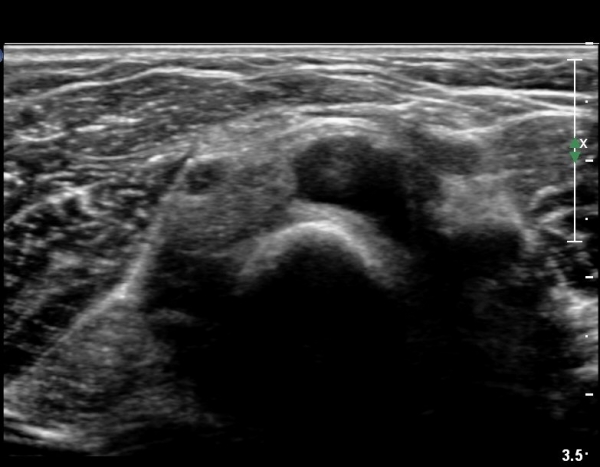

ÃÊÀ½ÆÄ °Ë»ç

¿Ü»ó°ú¿¡¼­ ¼Õ¸ñ ½ÅÀü°Ç ´ÜµÎ Á¾´Ü¸é°Ë»ç¿¡¼­ ƯÀÌ ¼Ò°ßÀ» º¸ÀÌÁö ¾Ê´Â´Ù(»çÁø 1, 2)

¿ä°ñµÎ ºÎÀ§ ÆÈ²ÞÄ¡ ¾Õ, ¿ÜÃø Ⱦ´Ü¸é°Ë»ç¿¡¼­ Èİñ°£ ½Å°æ ³»Ãø, ¿ä°ñµÎ Ç¥Ãþ¿¡¼­

ÀÛÀº ³¶Á¾ÀÌ °üÂûµÈ´Ù(»çÁø 3)